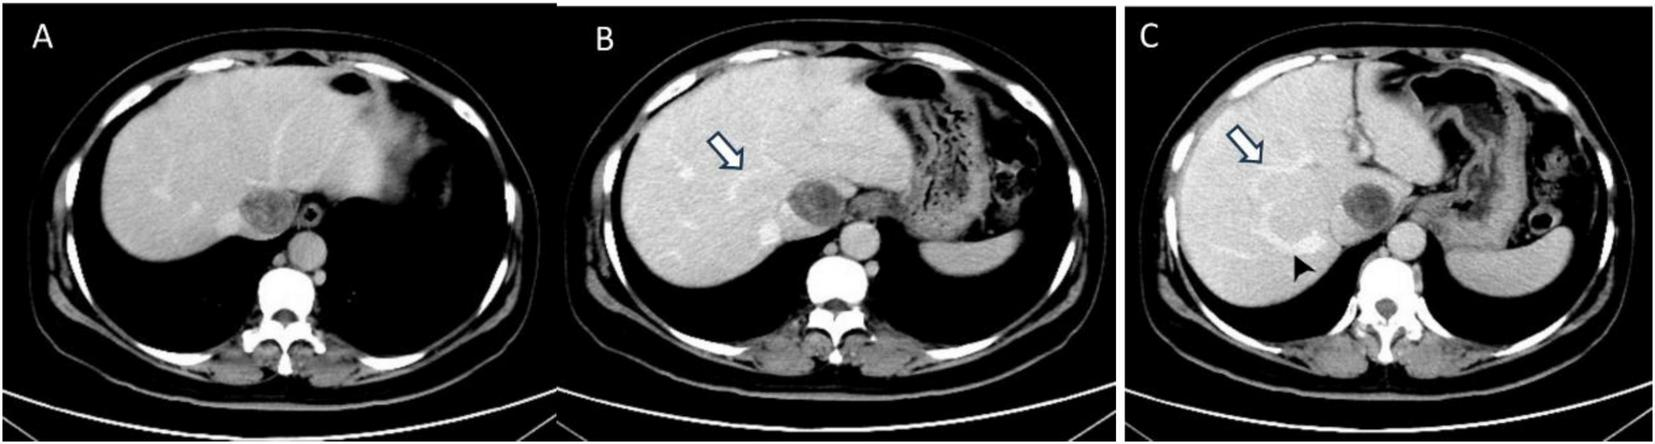

Abdominal enhanced computed tomography (CT) and inferior vena cava CT venography (CTV) demonstrated the presence of multiple soft tissue masses surrounding the uterus, extending from the left ovarian vein, left renal vein, and inferior vena cava to the right atrium (Figure 1). These masses exhibited slight enhancement. The second hepatic hilum was obstructed by the mass, resulting in a slender middle hepatic vein and a dilated accessory hepatic vein in the posterior right lobe. Additionally, the formation of communicating branches between the hepatic veins was observed (Figure 2).

FIGURE 2

The transverse sections of enhanced abdominal CT images. (A) The second hepatic hilum was obstructed by the mass. (B,C) Arrows demonstrated the presence of communicating branches between the hepatic veins. (C) The arrow head pointed the dilated accessory hepatic vein.